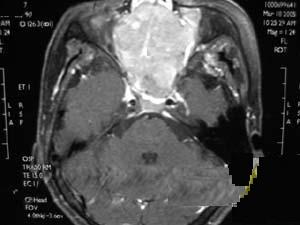

圖1 腦內脊索瘤成年患者有長期頭痛病史並出現一側展神經麻痹者,應考慮到脊索瘤的可能但確定診斷尚需藉助X線、CT和MRI等影像學檢查。

3.MRI:腫瘤多為長T1長T2信號,瘤內囊變區呈更長T1長T2信號,鈣化為黑色無信號影,出血灶則呈高信號注射Gd-DTPA後腫瘤輕度至中度強化(圖1)。